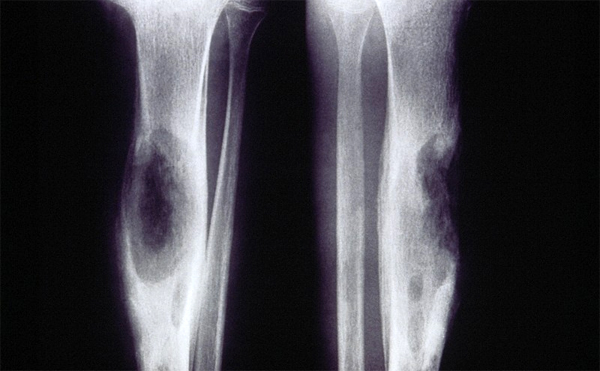

Рентгеновские снимки и визуализация болезни Педжета

Раздел: Мудрость в объективе